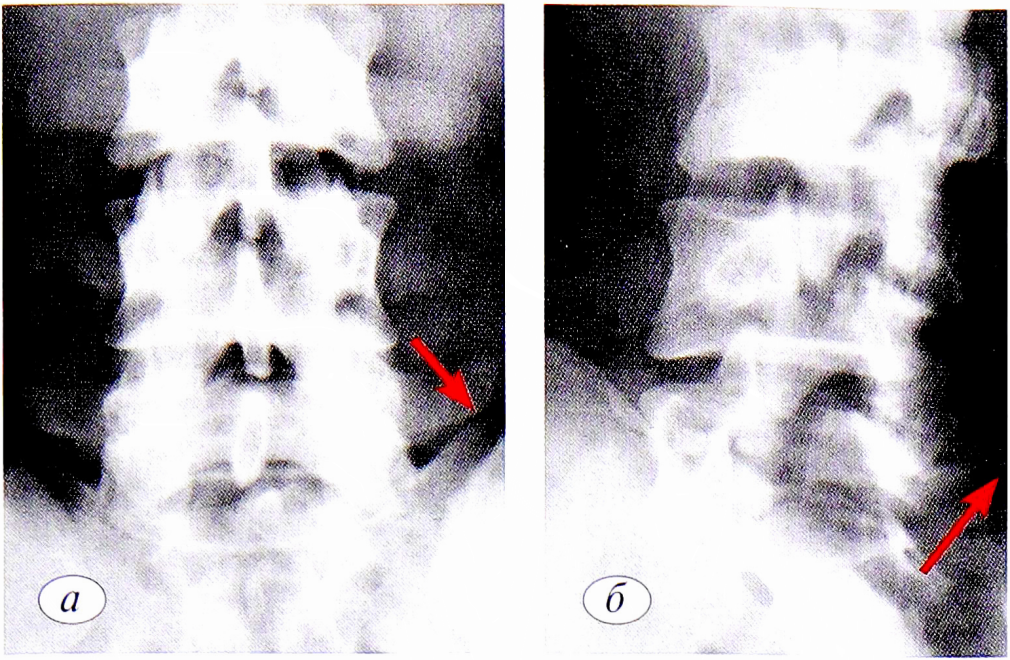

Сцинтиграфия с радиофармпрепаратом (РФП) 99mТс была выполнена 32 пациентам. При этом у пациентов с появлением поясничного болевого синдрома за 6 мес до обращения в клинику накопление РФП в области пораженной дуги превышало в среднем на 30%, от 6 мес до 1 года — на 10%, с длительностью заболевания более 1 года — отсутствовало. Контрольное исследование было произведено 24 пациентам в различные сроки после лечения. При коротком анамнезе отмечено снижение накопления до 15%, а при длительном — сцинтиграфические показатели практически остались без изменений (рис. 5).

Рис. 5. Сцинтиграммы при спондилолизе. а — гиперфиксация РФП при спондилолизе позвонка LIV; б— гипофиксация РФП при спондилолизе позвонка Lv. РФП — радиофармпрепарат.

Fig. 5. Scintigrams in spondylolysis. a — hyperfixation of radiopharmaceuticals (RF) in spondylolysis of vertebra LIV; b — hypofixation of RF in spondylolysis of vertebra LV.

Большое значение для ранней диагностики перестройки костной ткани в области дуг позвонков при соответствующей клинической картине и в отсутствие убедительных рентгенологических данных, а также для определения интенсивности минерального обмена этой области имеет сцинтиграфия [38—40].

Изображение перестроечного процесса в виде очага гиперфиксации РФП или, наоборот, гипофиксации его характеризуют повышение или снижение метаболических процессов. Данные сцинтиграфии могут быть информативными уже через 5—7 дней после травмы, приводящей к микропереломам, невидимым на обычных рентгенограммах. Позднее радионуклидное исследование позволяет следить за динамикой репаративных процессов и уточнить время возобновления профессиональных занятий. Согласно данным литературы, это исследование не показано при длительности поясничного болевого синдрома более 1 года или в отсутствие болевого синдрома [12, 29].

При всей своей информативности радионуклидное исследование недостаточно специфично, так как при гиперфиксации препарата трудно определить тип репаративного остеогенеза (патологическая или функциональная перестройка). Необходимо учитывать данные других исследований [41].